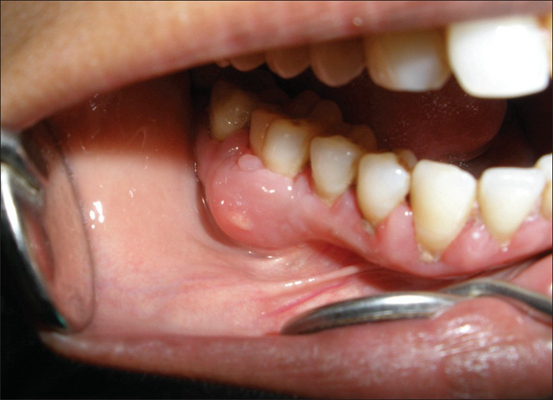

牙齦炎圖片

牙齦炎和牙周炎